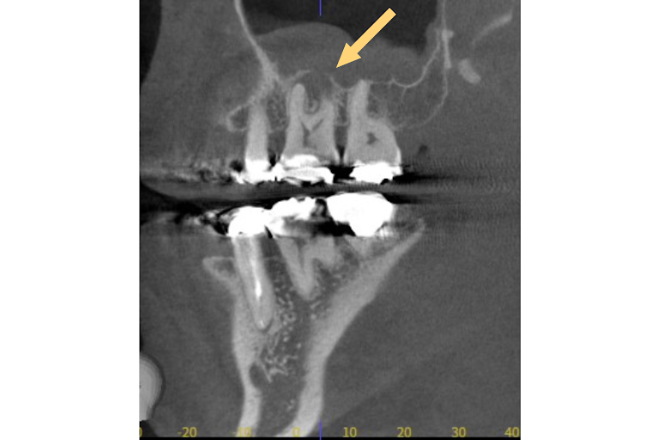

CT撮影やレントゲン撮影により、口腔内を詳細に検査します。

噛み合わせの詳細な検査を行い、顎関節の状態も確認します。

口腔内の総合的な診査により、患者様の状態を正確に把握いたします。